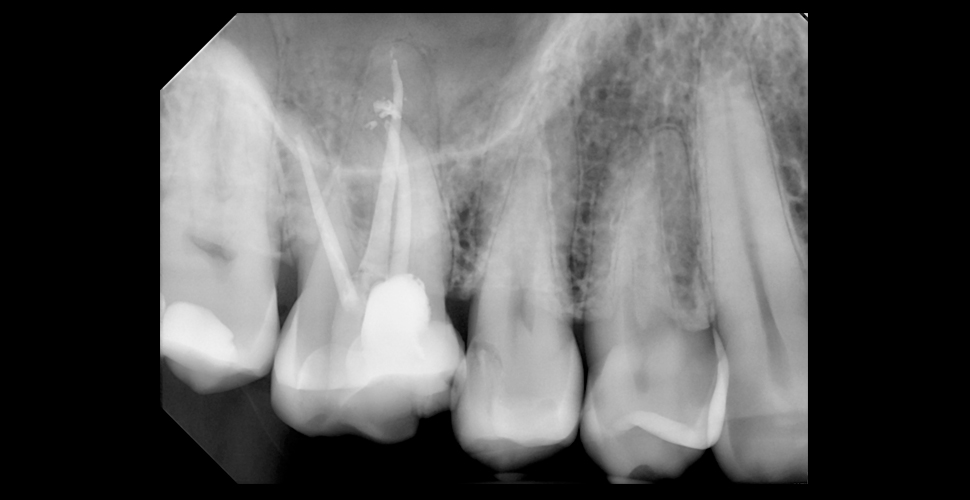

Есть ли разница в качестве изображения?

Качество снимков визиографа зависит от четырех факторов:

Качества и технических характеристик датчика,

Программного обеспечения,

Длины конуса, фокального пятна, силы тока, напряжения и др. характеристик рентгеновского аппарата,

Позиционирования сенсора.

Чтобы снимки были четкими, детальными и контрастными, рентген должен иметь специальный режим работы с визиографом, труба должна правильно располагаться относительно датчика, а сам датчик должен иметь порядка 16,384 уровней серого и разрешение от 17 пар линий.

В любом случае, лучше к хорошему дентальному рентгену подбирать недорогой надежный стоматологический визиограф, чем компенсировать плохое качество рентгена высококлассным датчиком и ПО.